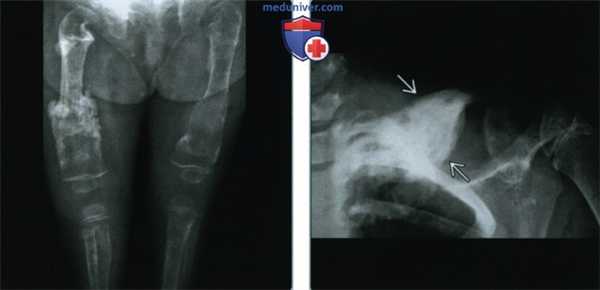

(Слева) Рентгенография в ПЗ проекции: определяется диффузный и тяжелый остеопороз с множественными переломами. Картина визуализации неспецифична, но в биоптате был выявлен мастоцитоз. Патологические изменения костей при детском мастоцитозе встречаются редко.

(Справа) Рентгенография в ПЗ проекции: определяется плотно-склеротичное изолированное образование с увеличением диафиза ключицы. Для такой картины визуализации предложен обширный дифференциально-диагностический ряд. У этого пациента отмечались нарушения пищеварения, которые появлялись эпизодически, как и сыпь. Такие симптомы позволяют сузить дифференциальный диагноз до мастоцитоза.